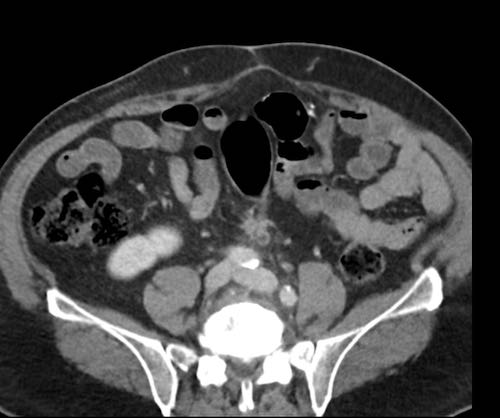

Ca lâm sàng 2

Cuộn qua các lát cắt.

Bạn có thể phát hiện tất cả các tổn thương cấy ghép phúc mạc không?

.jpeg)